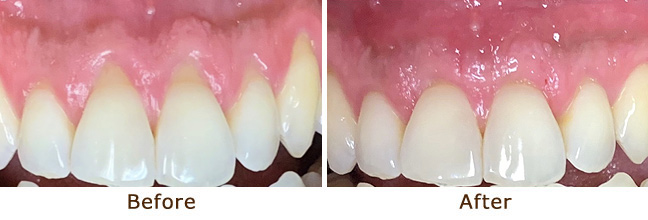

Gum Graft

Gum Graft

Gum Graft